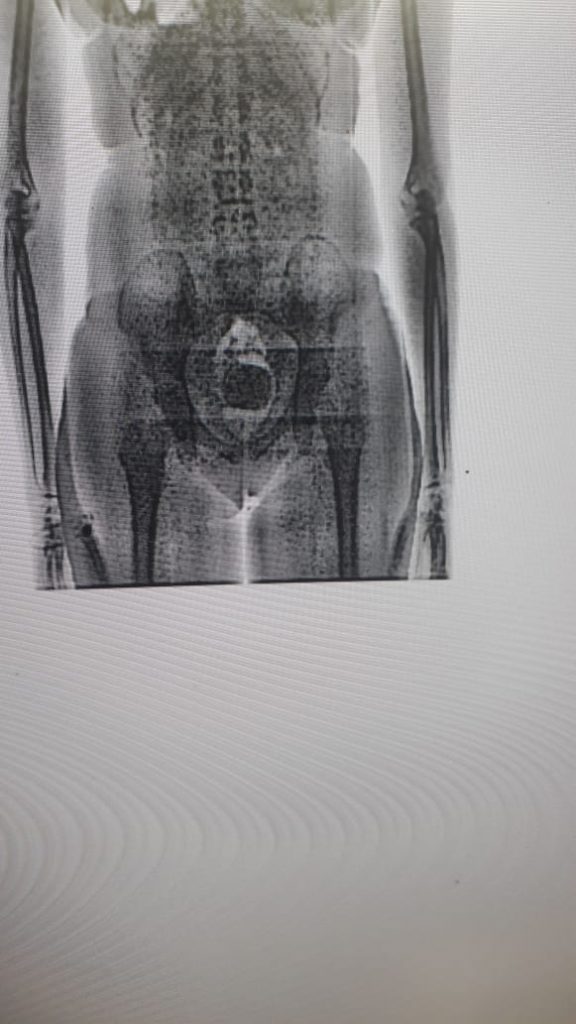

O coronel Reinaldo Chaves, secretário-executivo da Sejuc, explicou que, com a implementação do body scan, as revistas passaram a ser realizadas de forma totalmente digital sem a exposição dos visitantes a situações como a retirada de vestimentas. “O estado de Sergipe, desde o ano de 2017, com a aquisição dos aparelhos de body scan, aboliu qualquer tipo de revista vexatória. O scanner corporal é de alta tecnologia e consegue detectar a substância no interior do corpo humano”, destacou.

O secretário-executivo da Sejuc detalhou que os equipamentos fazem a identificação do material ilícito e geram as informações para a adoção dos procedimentos legais cabíveis a cada ocorrência. “A partir do momento em que é detectada a substância ou o material, é fotografado e arquivado, e a pessoa é encaminhada para o Instituto de Criminalística para perícia e os procedimentos são adotados na delegacia. As informações são encaminhadas ao Poder Judiciário”, especificou.